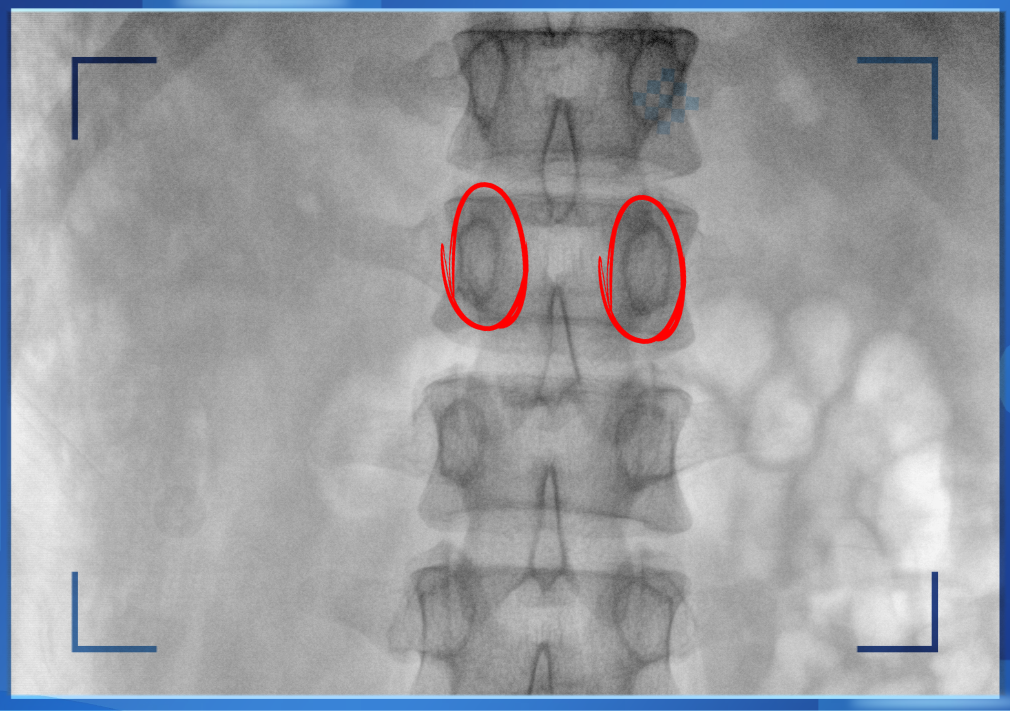

醫(yī)生通常會在“貓眼”里尋找進針點和出針點,憑醫(yī)生的經(jīng)驗把釘子打在椎弓根里。手術比較依賴醫(yī)生的經(jīng)驗,萬一出現(xiàn)偏差對病人來講就是毀滅性的打擊。如果在復雜的手術中有三維影像的支持,確保釘子精準的打在椎弓根里,可大大的提高手術操作的精度。

“貓眼”指的是椎弓根在正位的投影。